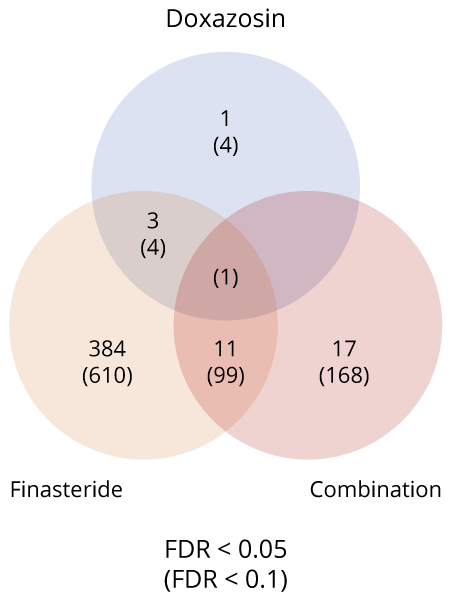

En el ensayo MTOPS, la administración de finasterida alteró > 400 genes en biopsias de zona transicional. Predominó la represión de:

- genes inmunorreguladores (Figura 1) [2].

Figura 1 Resumen del número de genes significativos que se superponen entre diferentes tratamientos (Un valor de FDR menor a 0.05 (FDR < 0.05) significa que, de todos los genes o vías declarados como significativos, se espera que menos del 5% sean falsos positivos).

SC1 consistía principalmente en pacientes tratados con finasterida o terapia combinada, mientras que SC2 estaba dominado por pacientes tratados con doxazosina o placebo. El cluster SC1 (86,8 % de los tratados) exhibió silenciamiento transcripcional y 90,1 % de éxito clínico; el cluster SC2 apenas modificó su perfil y concentró la resistencia (55,5 %) [2].

Figura 1 ilustra que la finasterida tiene un impacto mucho más amplio en la expresión génica del tejido de la zona transicional de la próstata que la doxazosina, y que la terapia combinada comparte una parte de este perfil genético alterado con la finasterida, lo que resalta la contribución dominante de la finasterida a los cambios moleculares observados en la terapia combinada.